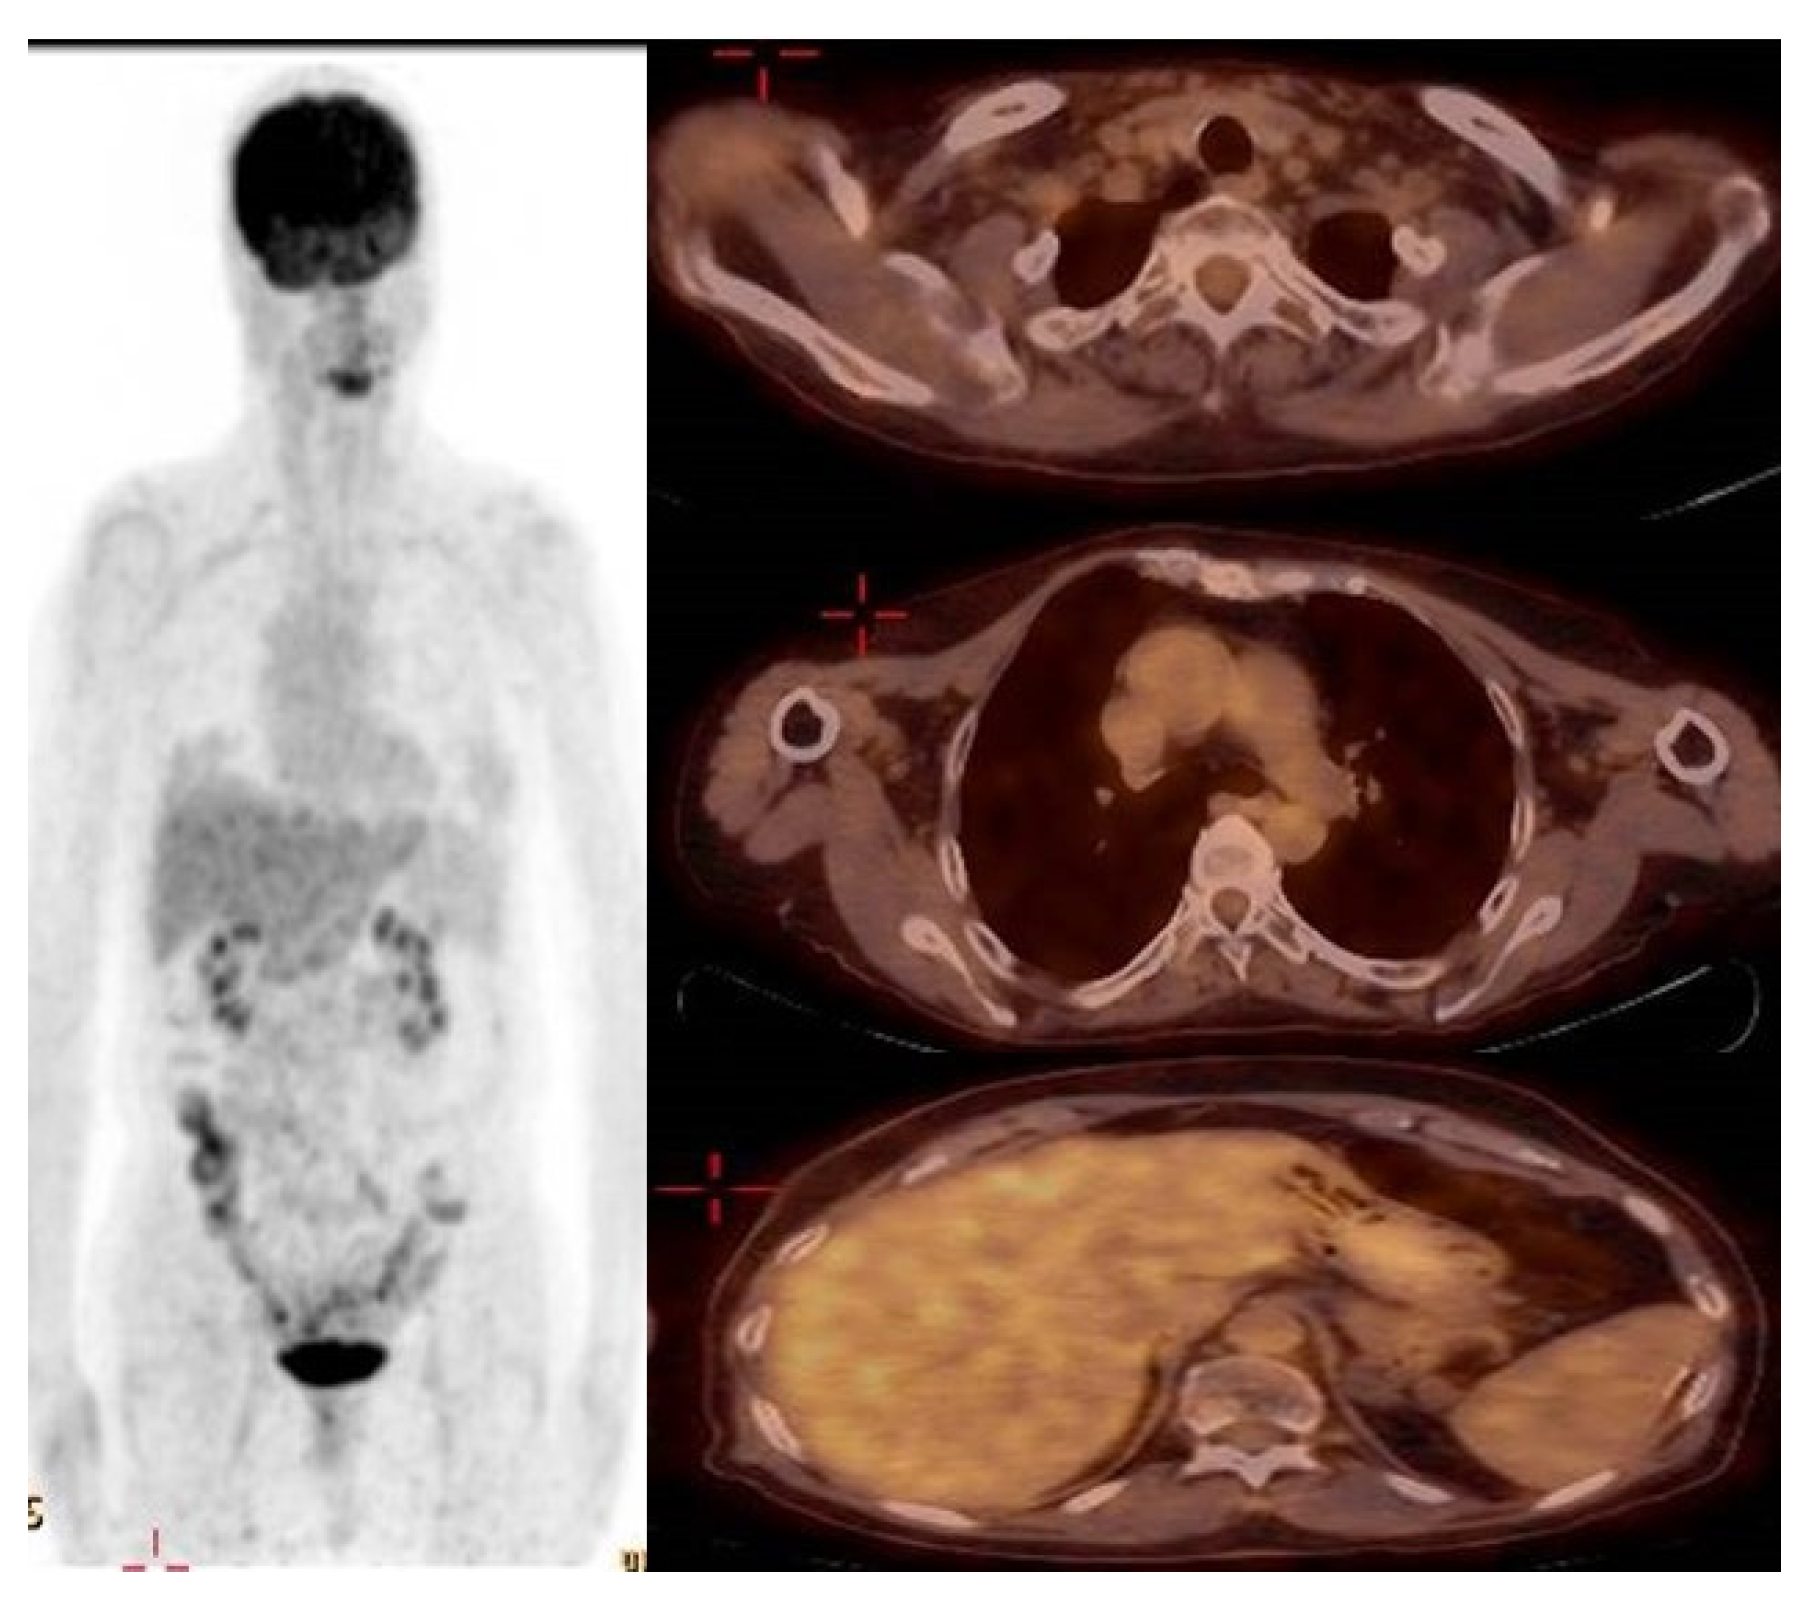

Following one month of Osimertinib administration (80 mg once a day), the patient’s dermatological symptoms improved, and two months later a PET-CT showed a radiological significant response (Figure 4). The left supraclavicular lymph nodes had receded in diameter with no pathological uptake. The mediastinal lymph nodes and the hilum of the left lung returned to normal size and were without pathological uptake. The LUL lesion had receded with lower pathological uptake. The splenic lesion had decreased in size without pathological uptake. (High muscle absorption was demonstrated due to a lack of fasting as required).

Figure 4.

PET-CT showing complete radiologic response to Osimertinib treatment.